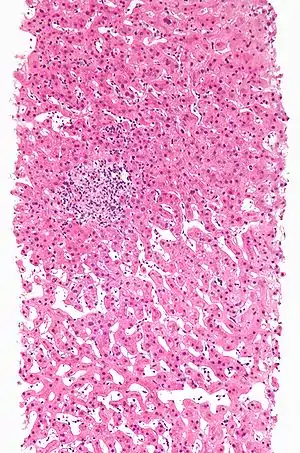

| Drug-induced hepatitis with granulomata. Other causes were excluded with extensive investigations. Liver biopsy. H&E stain. | |

Granuloma

Drug-induced hepatic granulomas are usually associated with granulomas in other tissues and patients typically have features of systemic vasculitis and hypersensitivity. More than 50 drugs have been implicated.

- Causes:

- Allopurinol, phenytoin, isoniazid, quinine, penicillin, quinidine